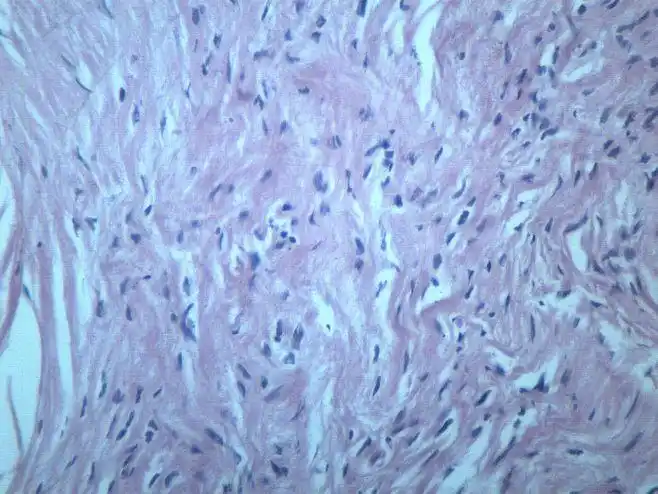

纤维瘤 显微图片